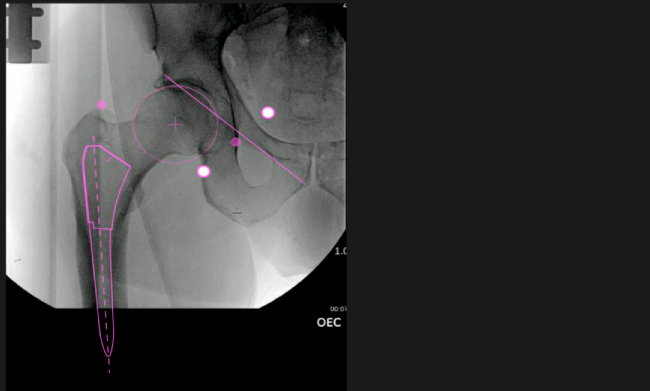

Planeación preoperatoria mediante la creación de plantillas digitales para reemplazo de cadera y análisis intraoperatorio

Mayor nivel de información intraoperatoria facilita la colocación correcta de los implantes:

Inclinación y anteversión de la copa acetabular para una correcta colocación del implante.

Desplazamiento y offset para posicionamiento óptimo del componente (vástago) femoral.

Anotaciones digitales y herramientas de análisis de longitud de pierna.